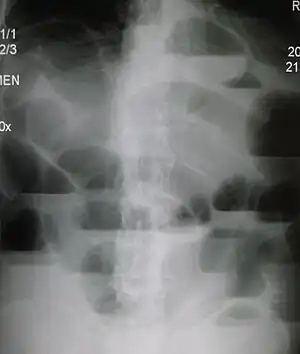

The main diagnostic tools are blood tests, X-rays of the abdomen, CT scanning, and ultrasound. If a mass is identified, biopsy may determine the nature of the mass.

Radiological signs of bowel obstruction include bowel distension and the presence of multiple (more than six) gas-fluid levels on supine and erect abdominal radiographs. Ultrasounds may be as useful as CT scanning to make the diagnosis.[13]

Contrast enema or small bowel series or CT scan can be used to define the level of obstruction, whether the obstruction is partial or complete, and to help define the cause of the obstruction. The appearance of water-soluble contrast in the cecum on an abdominal radiograph within 24 hours of it being given by mouth predicts resolution of an adhesive small bowel obstruction with sensitivity of 97% and specificity of 96%.[14]